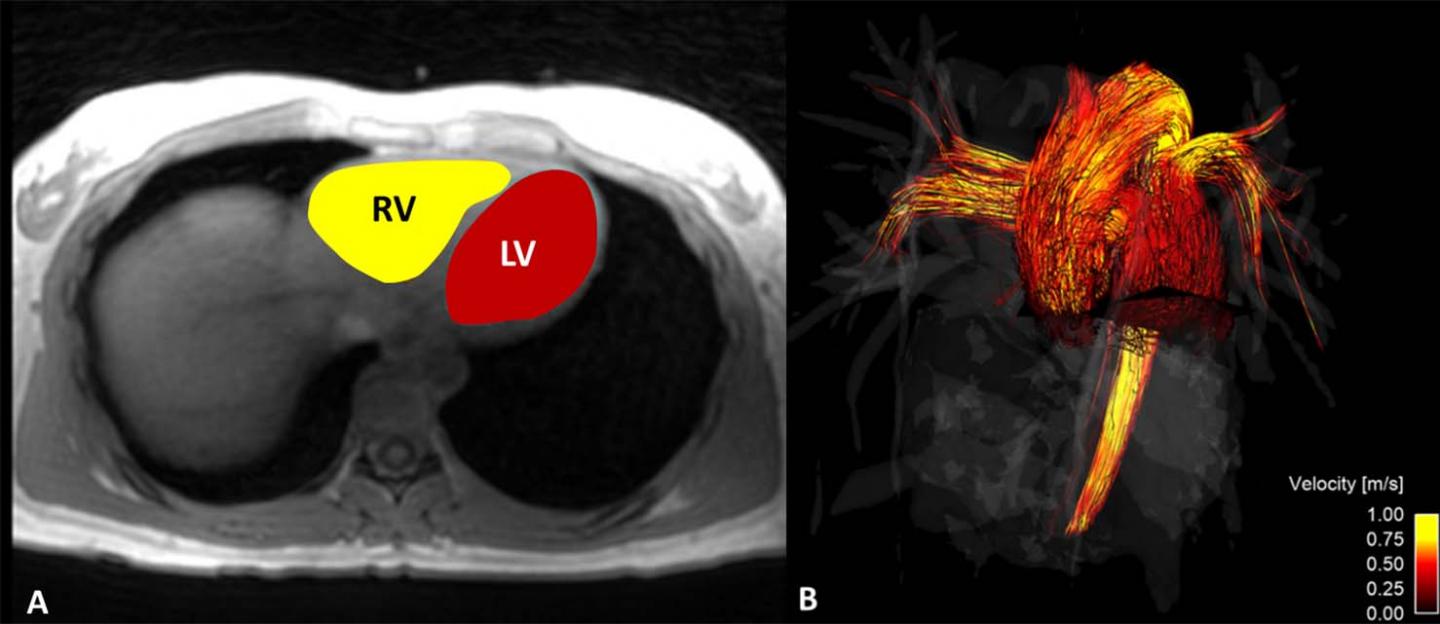

В новом исследовании использовалась сложная техника визуализации, которая называется МРТ 4D потока, для изучения работы левого желудочка – главной насосной камеры сердца.

В ходе эксперимента ученые следили за тем, как много молекул воды было в левом желудочке сердца их подопечных, и как быстро она покидала его во время каждого сокращения сердечной мышцы. Ученые получили различные параметры кровотока у мужчин и женщин, после чего сопоставили их с функцией сердца

Оказалось, что работа сердца мужчин и женщин несколько различается. Помимо повышенной напряженности стенок левого желудочка у женщин и большего числа завихрений в их крови, ученые обнаружили, что сердечная мышца мужчин тратит больше энергии во время сокращений, чем у представительниц слабого пола.

«Используя снимки МРТ, мы выяснили, чем отличаются сокращения сердца у мужчин и женщин. В частности, стенка левого желудочка женщин сильнее напрягается во время сокращений, а в крови при этом возникает больше вихревых течений. Мы предполагаем, что оба этих феномена связаны между собой», – прокомментировал работу ведущий автор исследования Дэвид Р.Рутковски.